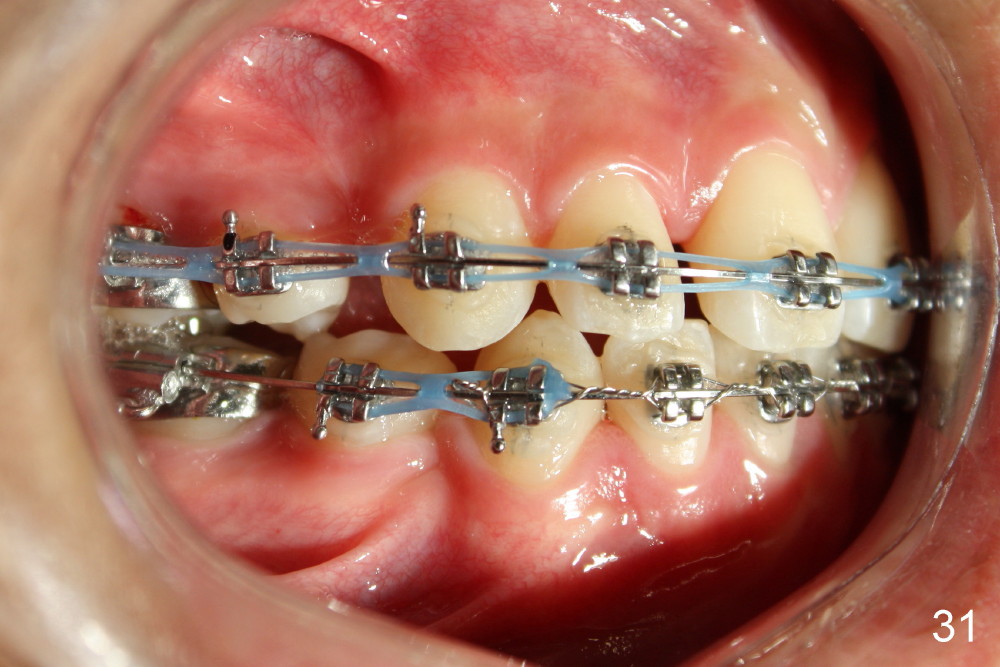

Prior to bracketing, the mesiodistal space for #18 is planned to be obtained by moving #20 and then #19 mesially (Fig.31-35, 16x16 ss). The six anterior lower teeth are tied together in a figure 8 fashion. Power chains are placed between the lower canine and the 2nd bicuspids. The upper diastemata are to be closed by power chains between the 1st molars.